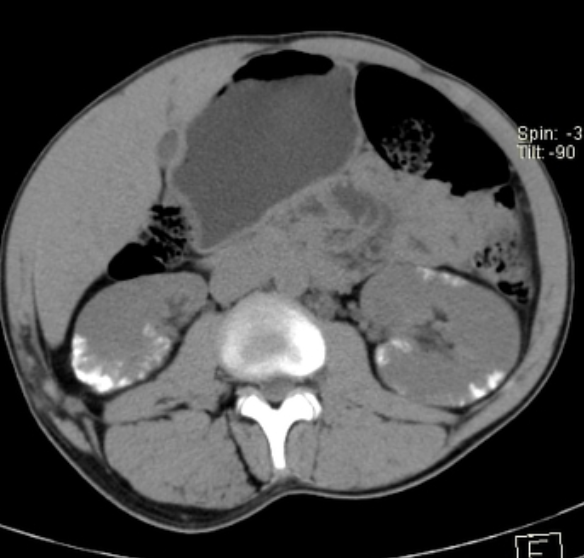

A

Cortical nephrocalcinosis (sequela of cortical necrosis)

Note: Cortical calcifications. Disseminated PCP and tuberculosis can look like this also.

Differential for cortical nephrocalcinosis

Acute drop I blood pressure:

• Shock

• Postpartum

• Burn patients